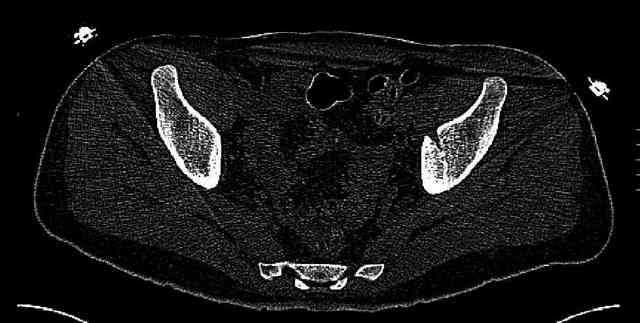

While not claiming to have the best 3D brain around, it appears to me from the limited images available, that the caudal segment is stable from the symphysis to the SI joint on the fracture side. I would love to see the rest of the transverse CT images to see where the fracture line actually exits posteriorly on both the inner and outer tables of the ilium. In my hands,

assuming that the femoral head has followed the cephalad (dome) fragment, I would use an ilioinguinal approach and take down the fracture line from anterior to posterior, distracting with a lamina spreader, if necessary, to clean out and inspect the joint. I would then reduce the cephalad fragment to the caudal fragment using jungbluth or farabeuf clamp and screws and then apply a plate and screws. If the fracture exits posteriorly would you then favor an additional posterior approach to clean out and reduce from that side?

Some more images. Does it help to guess which part of the acetabulum is displaced?

Normal appearing SI joints and a healed posterior column limb... my bet's on caudal segment displacement.